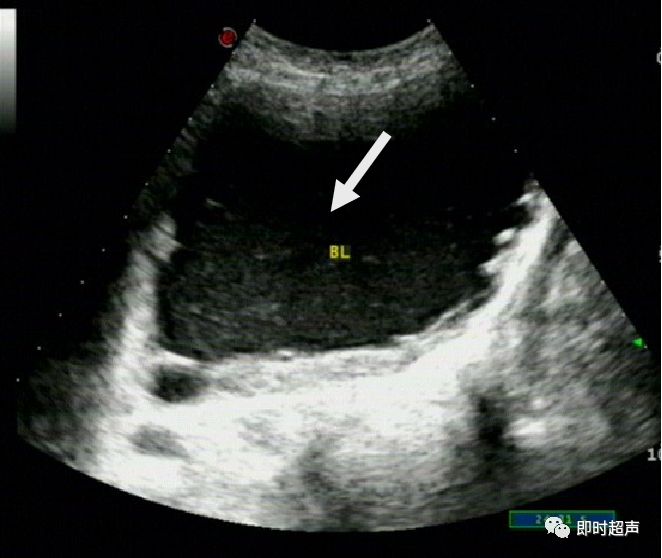

正常膀胱超声图像(经阴探测)

(膀胱壁呈中强回声光带,呈三层结构,分别由黏膜层(含黏膜下层)、肌层、浆膜层(含浆膜下层)组成,厚约0.1cm~0.3cm.膀胱内为无回声液性暗区 。经腔内扫查:能更清晰地显示膀胱壁的三层结构,(如图所示)尤其是检查膀胱后壁及三角区病变)

方法二:经腔内探测法:经直肠或经阴道探查膀胱,患者取截石位,探头作360°扫查(箭头),全面观察膀胱四壁.(要适当充盈膀胱,可详细观察膀胱壁的结构及病变的声像图特征。)